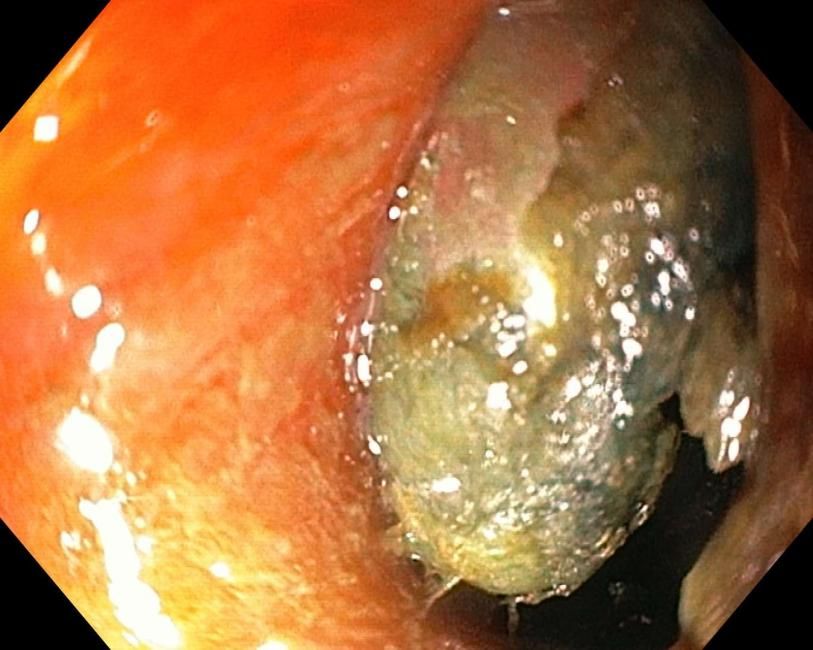

△腐蚀性异物-纽扣电池

△被电池腐蚀的消化道